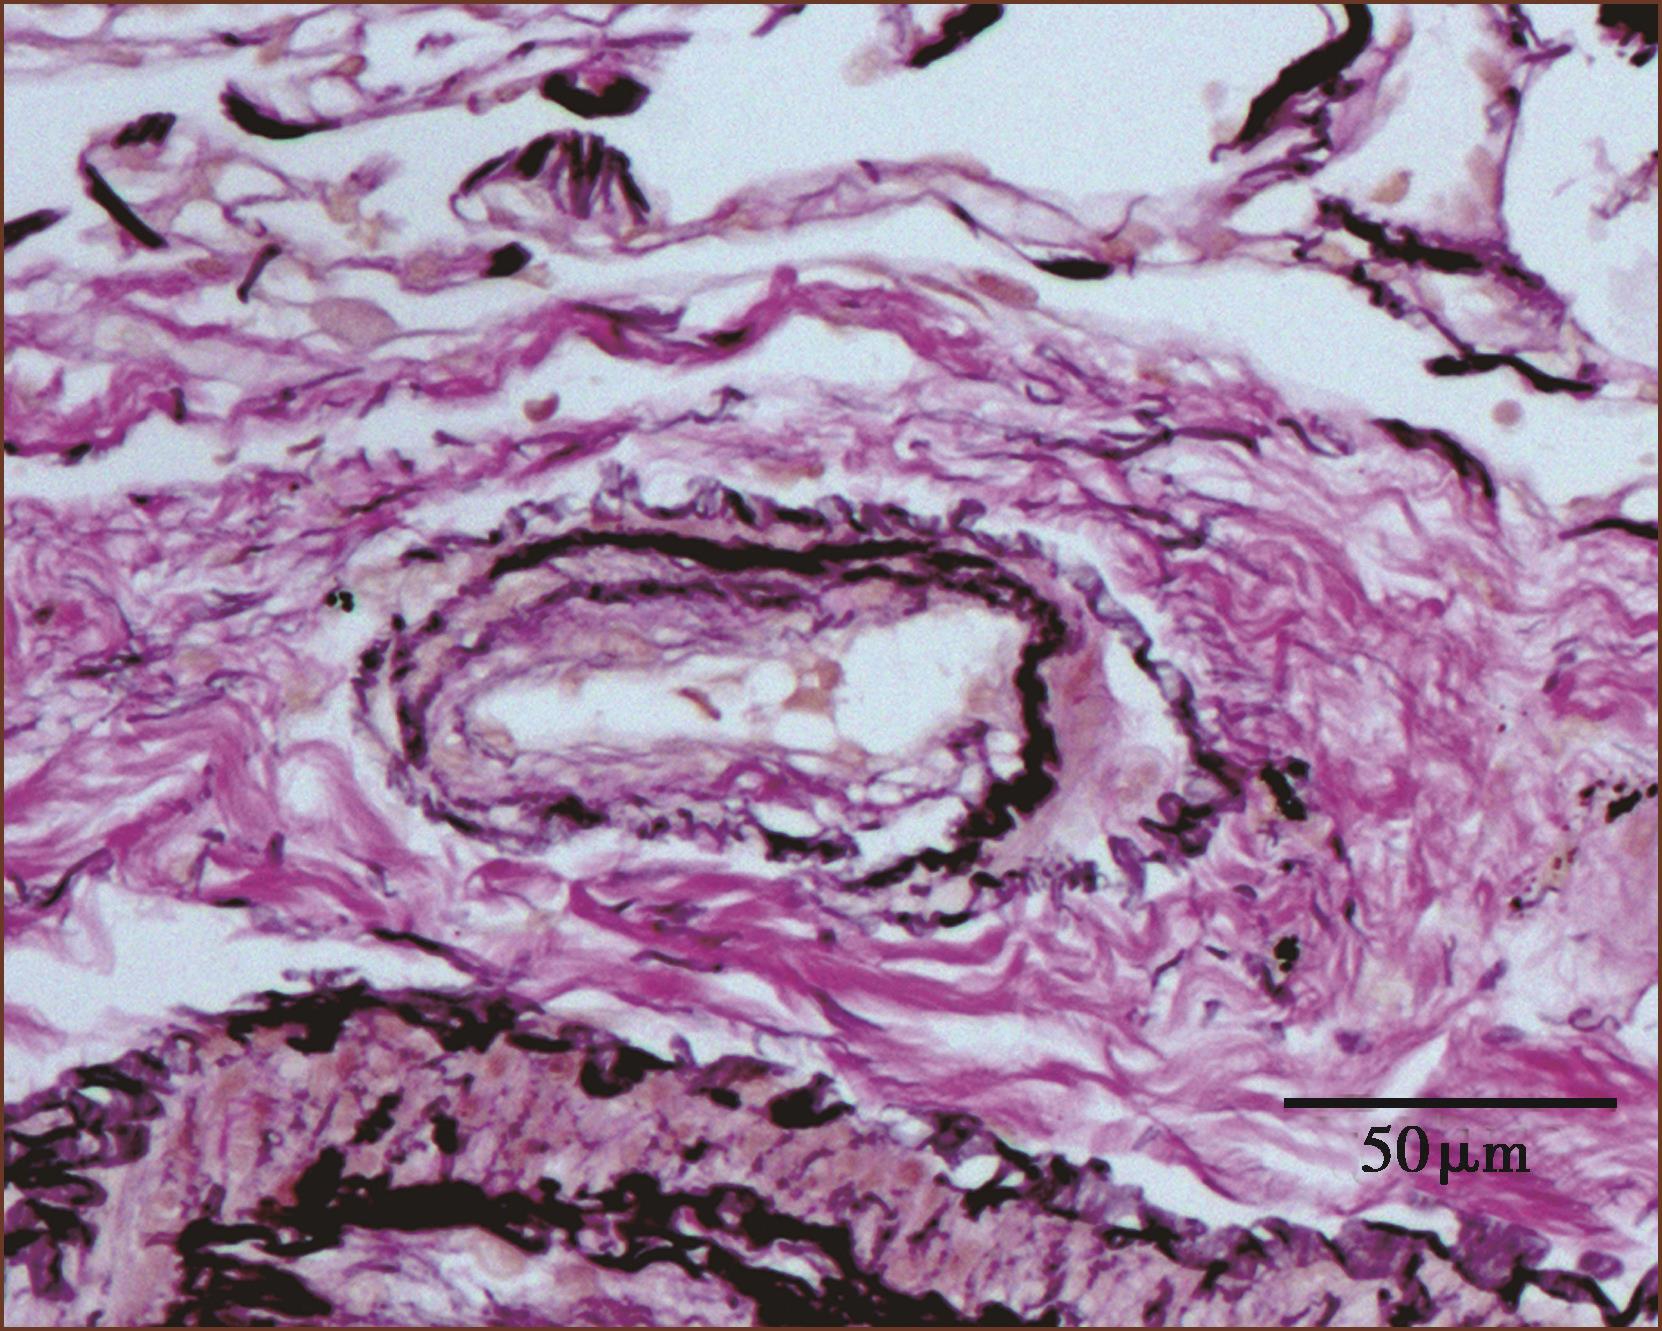

图1-3-3 肺肌型动脉

中膜含较多平滑肌,内外弹力板明显(ET+VG染色,中倍放大)

图1-3-4 肺微细动脉

中膜无完整肌层,内弹力板完整,外弹力板不完整(ET+VG染色,中倍放大)